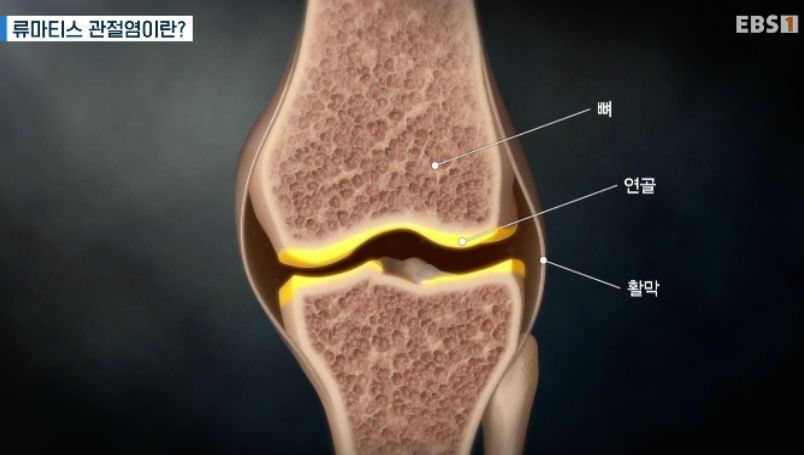

오작동한 면역세포가 관절의 활막을 공격해 변형시킨다.

침범돼 변형된 활막이 증식하고 관절에 물이 차 특유의 마디모양이 된다.

류마티스 관절염은

염증으로 커진 활막이

관절 주변을 파괴하는 병